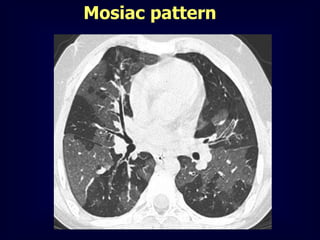

Mosiac pattern

Where is the pathology ???????

in the areas with increased density

meaning there is ground glass

in the areas with decreased density

meaning there is air trapping

Pathology in black areas

Airtrapping: Airway

Airway Disease

what you see……

In inspiration

sharply demarcated areas of seemingly increased

density (normal) and decreased density

demarcation by interlobular septa

In expiration

‘black’ areas remain in volume and density

‘white’ areas decrease in volume and increase in

density

INCREASE IN CONTRAST

DIFFERENCES

AIRTRAPPING